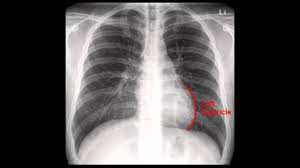

Interpretation of the chest x ray. Chest x ray is probably the most common imaging test. In addition to text and pictures, this tutorial contains interactive features which supplement the text and make it a more dynamic learning. Examination of the chest x ray is a process which requires a systematic approach. Standard frontal chest radiograph (roentgenogram) — upright; Recognizing normal anatomy on the cxr is key to understanding and interpreting abnormalities. Few providers (including mds) are comfortable interpreting their own films. In fact every radiologst should be an expert in chest film reading. Normal heart size is half of the chest width. Generally speaking, a normal cxr should have the lungs looking like zebras in that they are all black with strips. The aim of this study was to investigate the diagnostic accuracy of cxr interpretation by reporting radiographers (technologists). The chest radiograph remains the most important method of chest imaging, providing an easily accessible, inexpensive, quick, and effective diagnostic tool. Learn about chest x ray interpretation with free interactive flashcards.

Normal heart size is half of the chest width. Standard frontal chest radiograph (roentgenogram) — upright; In fact every radiologst should be an expert in chest film reading. Generally speaking, a normal cxr should have the lungs looking like zebras in that they are all black with strips. These images were saved with anonymous biodata for iom radiology collection and teaching purposes.